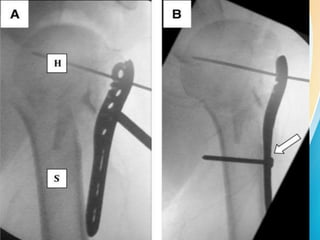

INTRA OPERATIVE IMAGE

INTENSIFIER(C-ARM)

2 views

1) plate view :-

• arm is placed on an internally rotated position

• allows us to see the full profile of the plate

• plate should lie opposite and be centered over

the humeral head-should have light bulb

appearance.

45 DEGREES INCLINATION OF C-ARM

2) screw view :-

• it is the position in which articular surface

maximally purchased to the glenoid.

• arm is externally roatated to approximately

20-30degrees